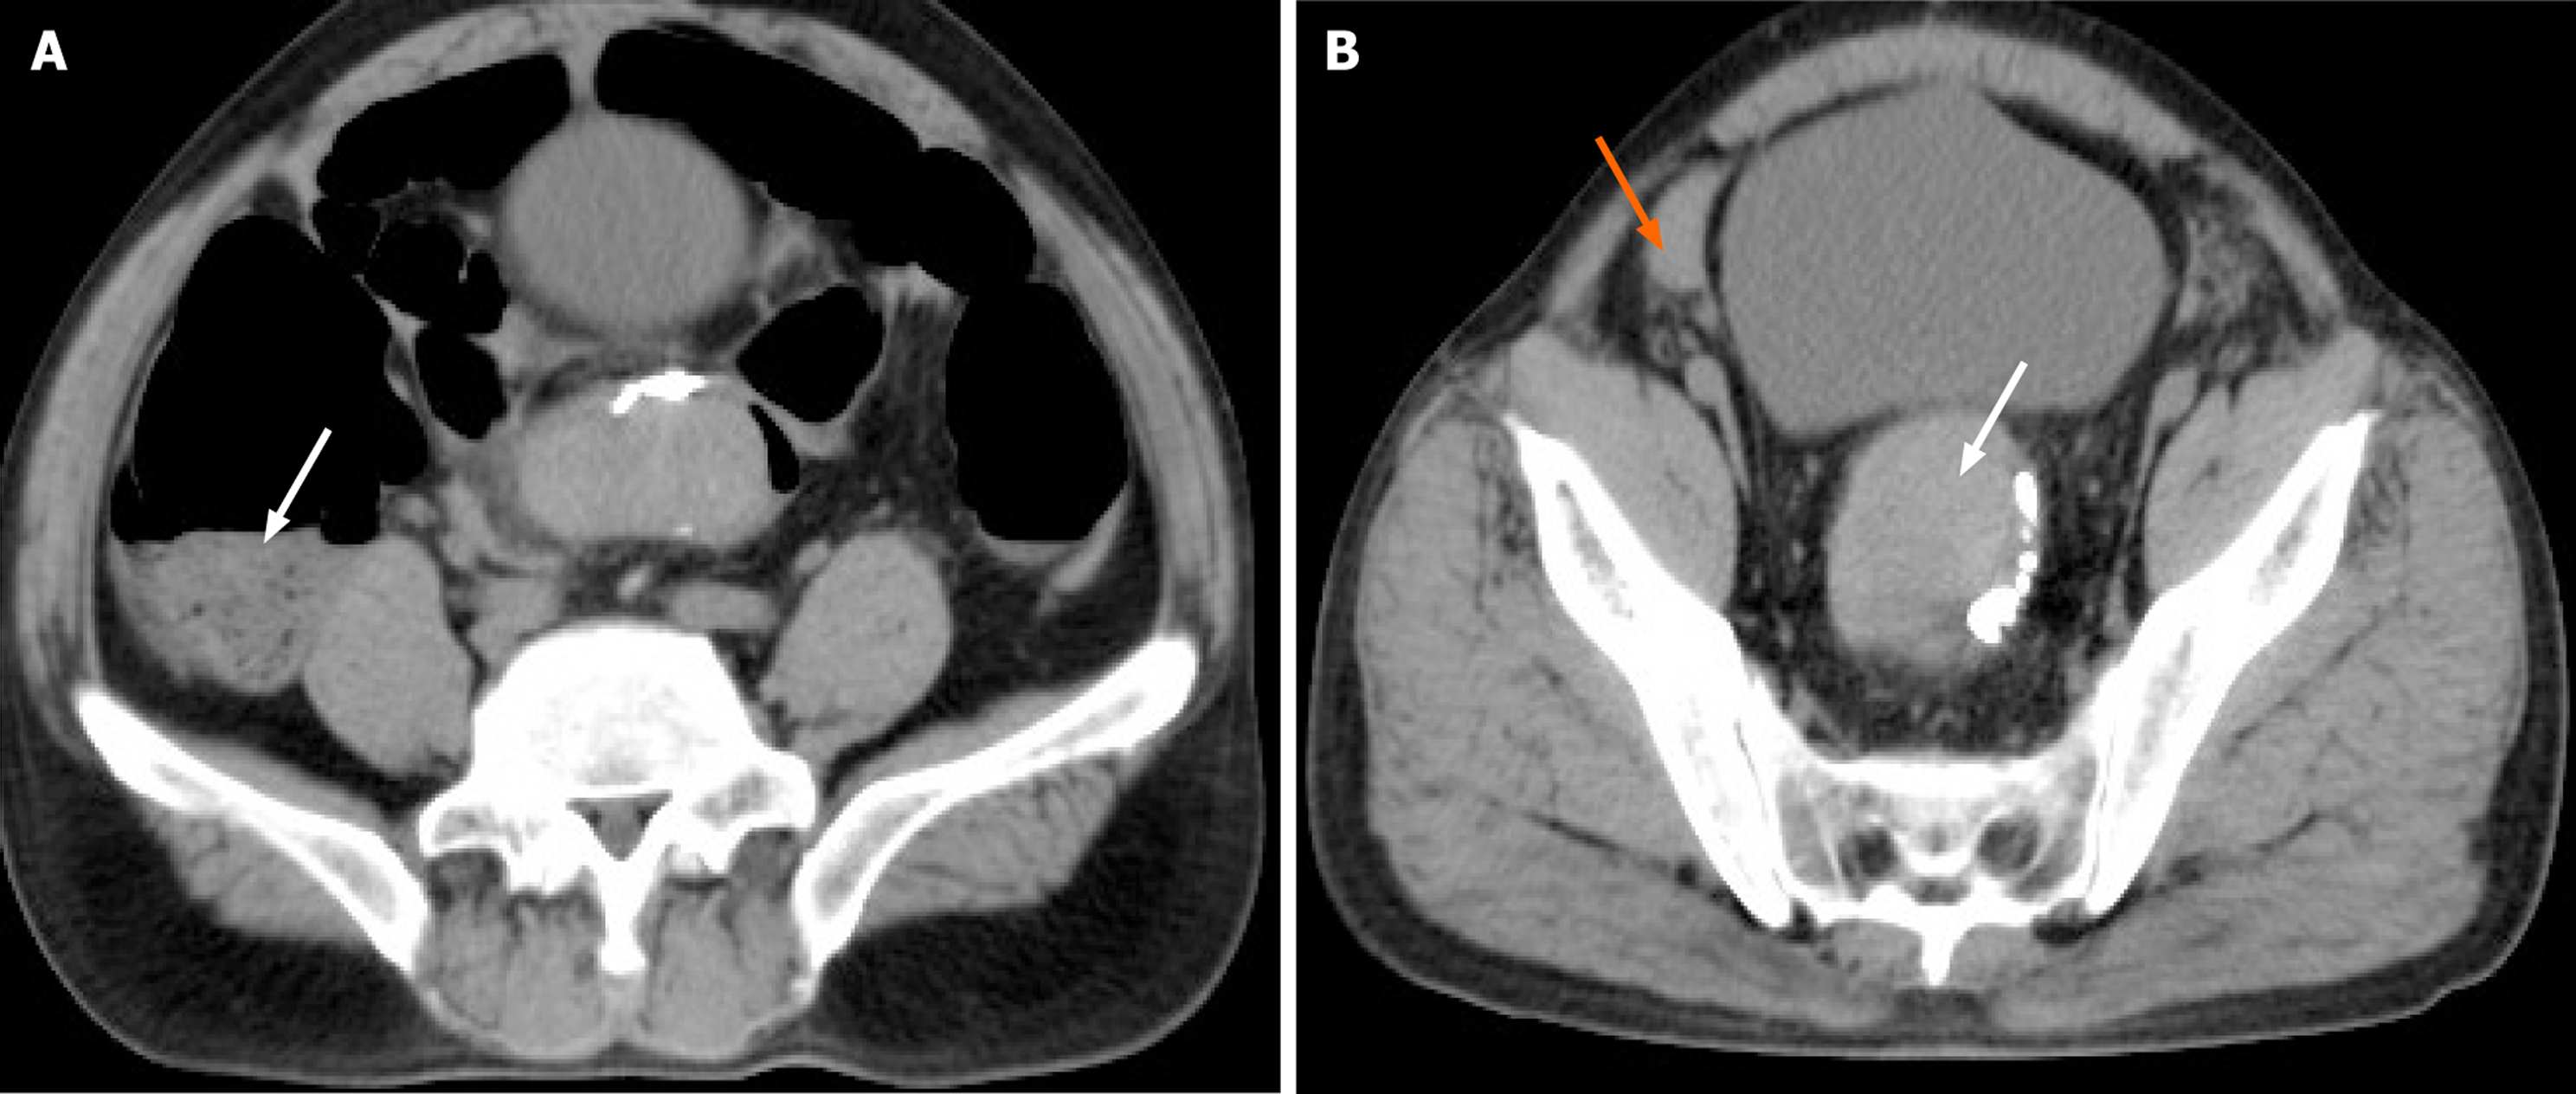

Figure 2 Computed tomography scan on postoperative day 4.

A: Intestinal air-fluid level (white arrow); B: Rectal hematoma (white arrow) and hemo peritoneum (orange arrow).